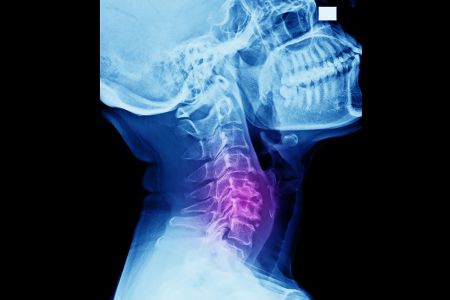

Cervical spondylotic myelopathy is a condition of the neck that arises due to wear and tear when the spinal cord is squeezed or compressed and is associated with aging.